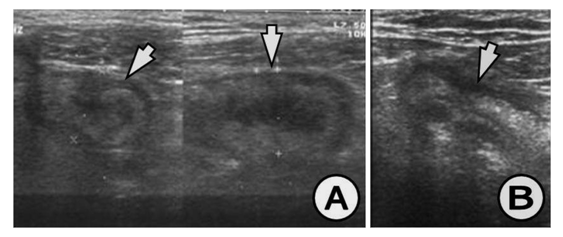

The appendix on US study is demonstrated by: hypo echoic lumen, hyper echoic mucosa, iso echoic lamina propria, hyper echoic submucosa, hypo echoic muskularis and hyper echoic serosa. The increased size of the appendix is a sign for phlegmonous or gangrenous appendicitis (Figure 1). The present appendicolith is demonstrated as hyper echoic mass that fills in the lumen and gives acoustic shadow (Figure 2B). When the appendicolith should be visualized, the wall thickness and the compressibility are not the features for making the diagnosis of acute appendicitis. The gangrenous appendicitis has changes in echogenity in all layers and the same are with the uniform echogenity and cannot be distinguished (Figure 3A). If the ill defined or hypo echoic mass is seen that surrounds the appendix that presents the periappendiceal inflammation (Figure 4). The ill defined appendiceal wall is suggestible, but not diagnostic for the periappendiceal process. The fluid presence into the appendiceal surrounding, with appendiceal wall echogenity changes is US feature for perforation (Figure 3B). The positive lymph nodes are oval hypo echoic and they don’t change the shape on compression.

Figure 3 (A) Appendix in saggital and coronal plane, thicken and oedematous wall, with widen lumen, disturbed appendiceal architecture and surrounding infiltration, US finding for gangrenous appendicitis, (B) Appendix with thickened wall, widened lumen and periappendiceal fluid, US finding for gangrenous appendicitis.

Figure 4 (A) Coronal view, appendix with thickened wall and surrounding infiltration, (B) Saggital view, appendix with thickened wall and surrounding infiltration, US finding for appendiceal phlegmon.